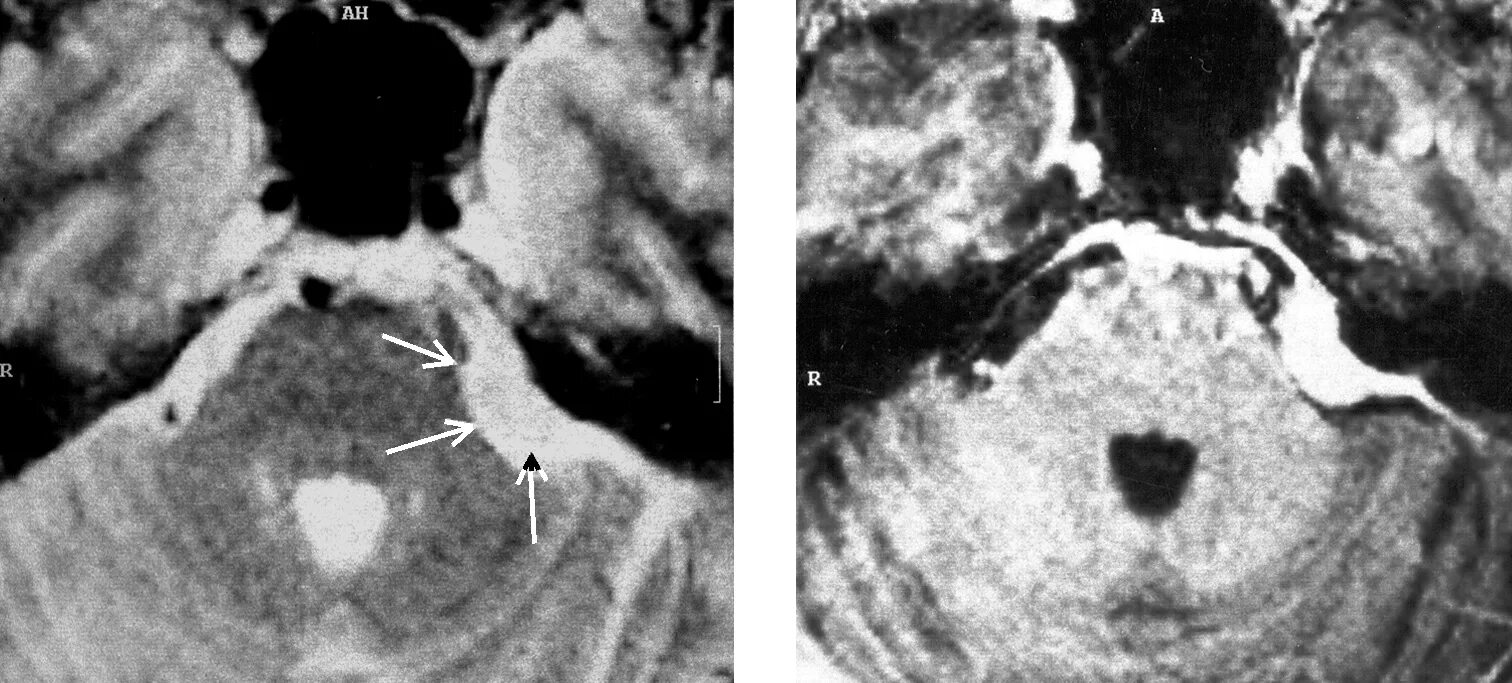

Мрт головного мозга мосто мозжечкового угла